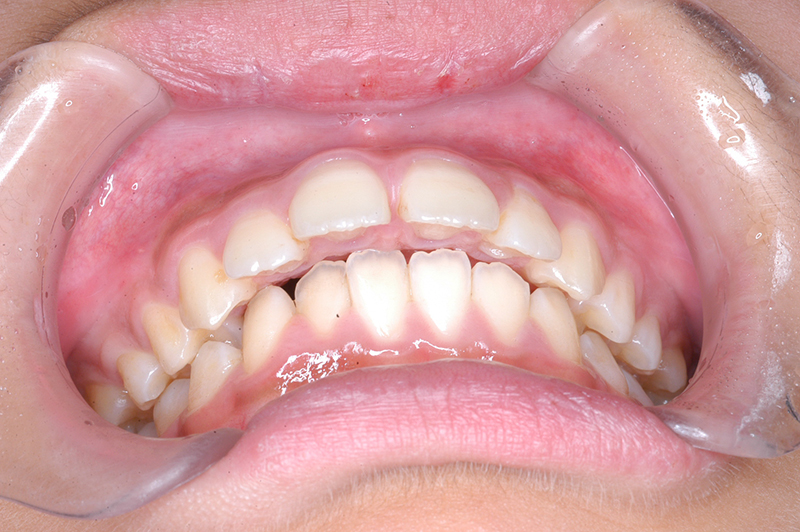

初診時

主訴 出っ歯 診断名 アングルⅡ級1類

初診時年齢 10歳2ヵ月 性別 動的治療期間 23ヵ月

口腔内所見 大臼歯関係は右側がエンドオンのclassⅡ、左側がfull classⅡ。 上顎正中は下顎正中に対して僅かに右側偏位しており、上顎前歯は大きく唇側傾斜しover jetが11.0mmと上突咬合を呈していた。また下顎歯列の緩やかなスピーカーブのため過蓋咬合(over biteは5.0mm)となっていた。